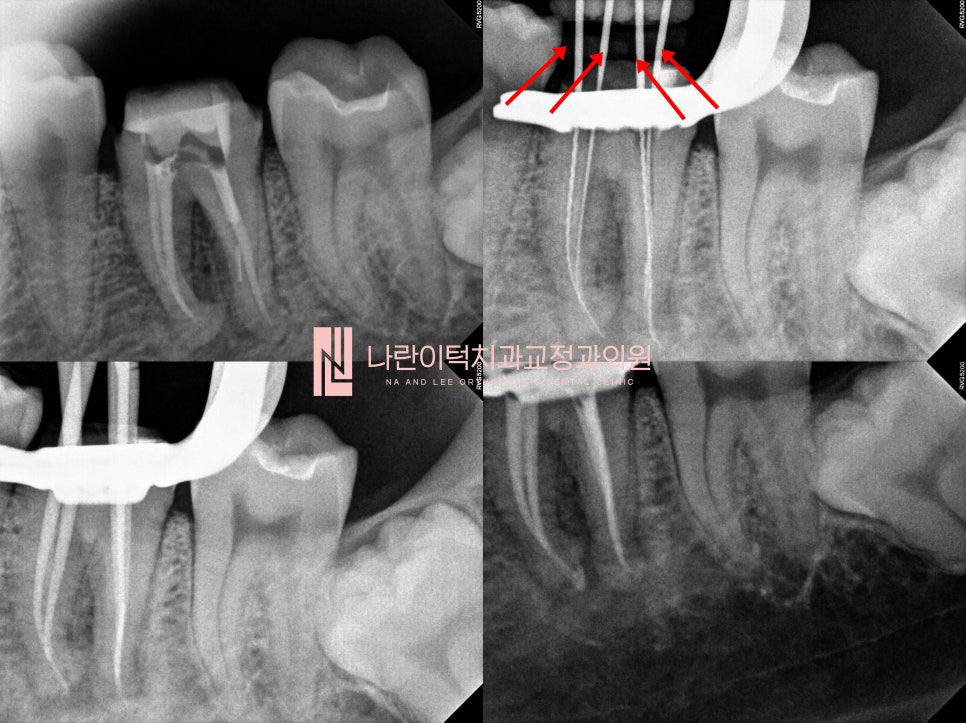

[재신경치료 Root-canal treatment]

조심스럽게 크라운을 제거하니 오염된 레진코어가 보입니다. 우측 큐레이 사진에서 빨갛게 보이는 부위들은 모두 세균입니다!

하지만, 뿌리끝 염증이 될만큼의 큰 문제는 아닙니다.

조심스럽게 재신경치료 진행하였고, 기존 3개 신경관의 신경치료 이외에 찾지 못한 1개의 신경관을 더 찾아

총 4개의 재신경치료가 진행되었습니다. (빨간화살표)를 통해 4개의 신경치료기구가 잘 들어간 것을 확인할 수 있습니다.

일주일 간격으로 신경치료를 통해 치아 내부를 세척해주니, 2주만에 저작 시 통증이 사라졌습니다.

이때 신경치료를 마무리 해줍니다.

총 4개의 재신경치료 뿌리입구가 잘 밀봉되었습니다.(빨간화살표) 큐레이로 확인하니 추가적인 실금은 보이지 않습니다.

(실금이 있다면 아무리 재신경치료를 잘 하였더라도 증상이 지속되거나 실금이 뿌리끝까지 진전되어 파절될 수 있기 때문에! 실금을 찾는 것은 굉장히 중요합니다.)

레진이라는 재료로 치아입구가 잘 밀봉되었습니다. (노란점선)